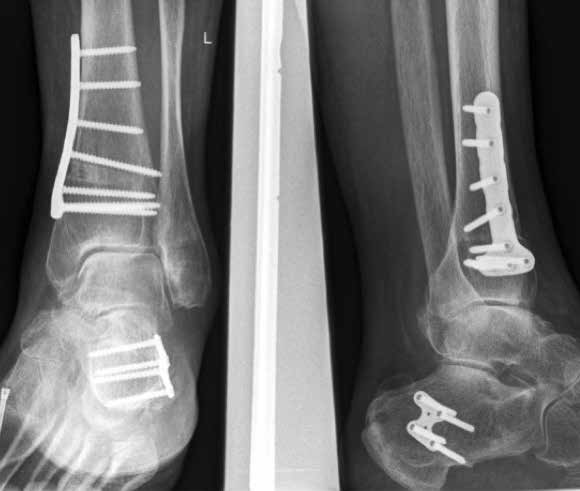

Arthrodese

In ausgeprägten Fällen von Arthrose, oft mit Instabilität im oberen Sprunggelenk (Abb. 7), schwerwiegendem Funktionsverlust und starker Schmerzausprägung, ist nach wie vor die Arthrodese die Therapieoption der Wahl. Dadurch sollen die Achskongruenz wiederhergestellt und die Schmerzen eliminiert werden. Gleichzeitig bedeutet dieser Schritt jedoch, dass keine weitere operative Eskalation mehr möglich ist. Meist kommen die tibiotarsale oder tibiatalar-calcaneare Arthrodese zum Einsatz. Entscheidend für die Wahl des Arthrodeseverfahrens sind der Schweregrad der degenerativen Gelenkveränderungen, der Schmerz und die Stellungsverhältnisse im Subtalargelenk.

Eine Sonderform stellt die Talusnekrose dar, die ebenfalls zu schwerwiegenden Destruktionen und Achsfehlstellungen im OSG führt. Das Mittel der Wahl im fortgeschrittenen Stadium (Abb. 8a) ist hier die Arthrodese des OSG und des unteren Sprunggelenks (USG) mittels Arthrodesennagel (Abb. 8b).